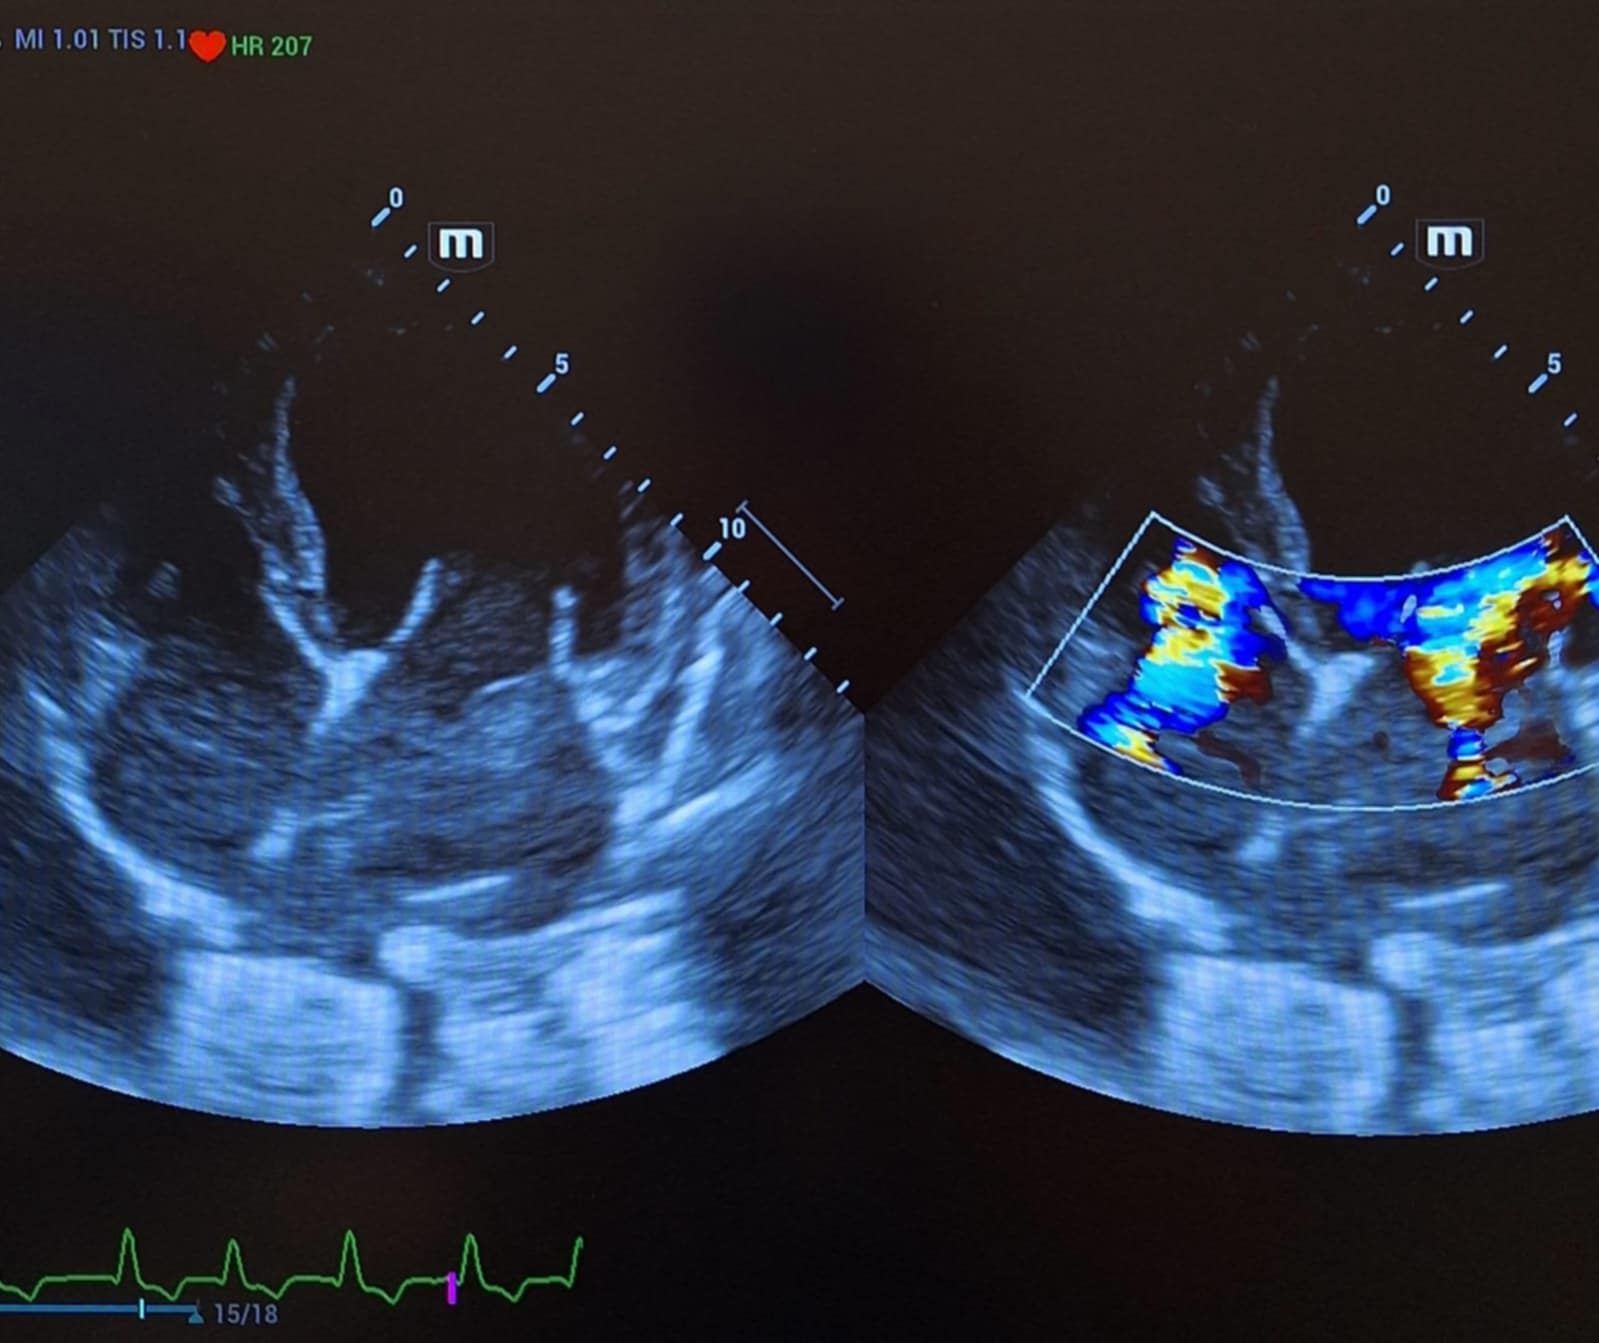

• echo serca z badaniem dopplerowskim ( usg serca)